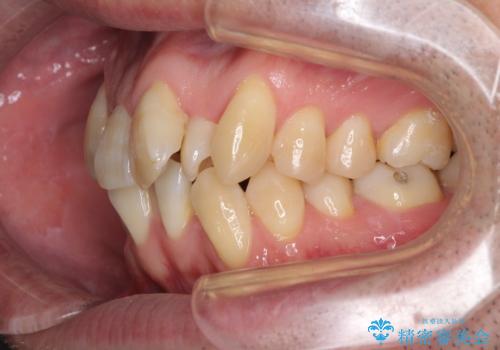

- 前歯のデコボコを気にして来院された患者様です。

叢生の解消とともに、前方に張り出した上顎前歯を引っ込めることを目的とし、上下左右の第一小臼歯4歯を抜歯をしてワイヤー矯正により治療することとしました。